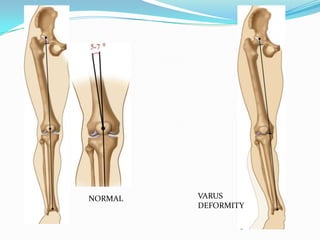

NORMAL VARUS

DEFORMITY

 Credited toJackson and Waugh (1961)  High tibial osteotomy (HTO) corrects alignment of the knee, relieving pressure from the arthritic portion of the joint, and transferring it to an area of more normal cartilage.  This frequently leads to pain relief and, subsequently, improved function.  Well established procedure for unicompartmental arthritis with 80 % satisfactory results.  Biomechanical basis  unloading of the affected compartment